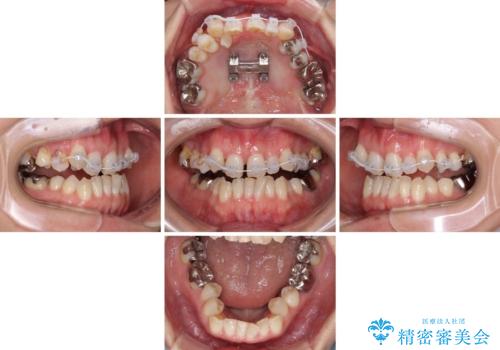

上顎骨の幅が下顎骨よりも小さいので、拡大装置により骨幅を広げて上下関係を改善すると同時にワイヤー矯正で反対咬合の改善を図り、その後インビザラインにて歯並びを整えることとしました。

上顎前歯の矮小歯は矯正治療の途中でオールセラミッククラウンを装着し、左右のバランスを整えることとしました。

急速拡大装置の使用により奥歯の咬み合わせが劇的に変わり、その変化を利用して反対咬合を改善することができました。

治療期間中は奥歯が咬み合わず、食事が取りにくいなどの不都合がありましたが、最終的にはきれいに整えることができました。